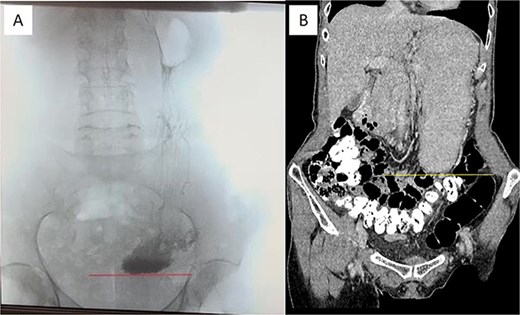

At this admission, the patient reported feeling “Bloated in the stomach, unable to eat solid foods, belching, bitter taste in the mouth, and weight loss (7 kg). BMI was 16.1 upon admission and showed signs of malnutrition” (Fig. 1). Gastric and duodenal radiography on 1 April 2025 showed the distal stomach located in the pelvic projection range, and the stomach had not emptied after observation for 2 hours (Fig. 2A). Combined X-ray and computed tomography (CT) findings revealed severe gastroptosis (Fig. 2B), and repeat endoscopy indicated pyloric obstruction, with difficulty passing the endoscope through the pyloric ring. Ulcer stenosis at the ESD site led to deformation of the gastric antrum and GOO, with chronic food retention and continuous gastric acid stimulation causing scar healing (Fig. 3). Given the extensive stenosis, EBD treatment was deemed likely ineffective. Prior to surgery, and to compensate for the nutritional deficiency, the patient received enteral nutrition with “Leovit ONCO” according to the clinic’s protocol, and laparoscopic-assisted distal gastrectomy with Billroth I anastomosis was planned.

Pre-operative imaging confirming GOO. (A) X-ray of the stomach and duodenum with contrast medium. Line indicates the lower border of the stomach. (B) CT scan of the abdomen with intravenous contrast. Line demarcates the lower border of the stomach.